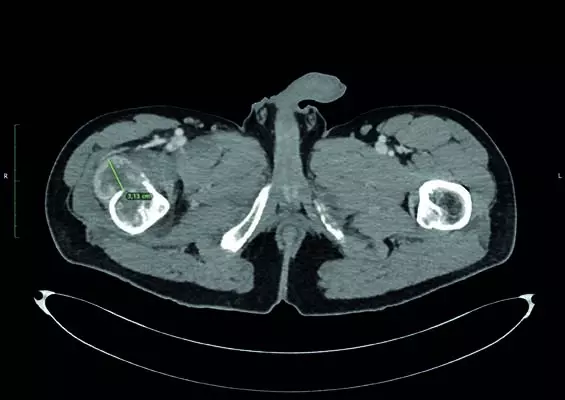

Na łamach najnowszego wydania czasopisma Praktyczna Ortopedia i Traumatologia poruszamy temat nowych technologii w ortopedii: zastosowanie okularów mieszanej rzeczywistości (MR) podczas operacji resekcji przerzutu raka jasnokomórkowego nerki do kości udowej. Zastosowanie okularów MR umożliwia realistyczne planowanie operacji, ułatwia resekcję guza, resekcję kości i wpływa na zmniejszenie czasu operacji, utratę krwi i zmniejszenie ryzyka infekcji. Opisujemy także wybrane problemy skórne u pacjentów ortopedycznych, które są dużym problemem komplikującym często leczenie zabiegowe. Najczęściej związane są z zakażeniami skóry i tkanki podskórnej oraz reakcjami nadwrażliwości związanymi z kontaktowym alergicznym i niealergicznym zapaleniem skóry. Zapraszamy do lektury!